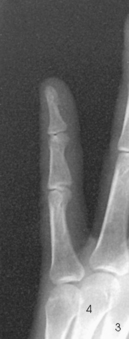

Structures shown: This projection shows the MCP joints and MCP angles bilaterally (Fig. 4-52).

Fig. 4-52 First MCP joint, Folio method. A, Normal thumbs with acceptable MCP joints bilaterally. Roll of tape between metacarpals and rubber band holding distal aspects of thumbs are visible. B, Increased angulation of left MCP joint with 13-degree difference compared with right MCP joint. Partially torn left UCL measures 20 degrees between long axis of first metacarpal and proximal phalanx, whereas uninjured side measures 7 degrees.